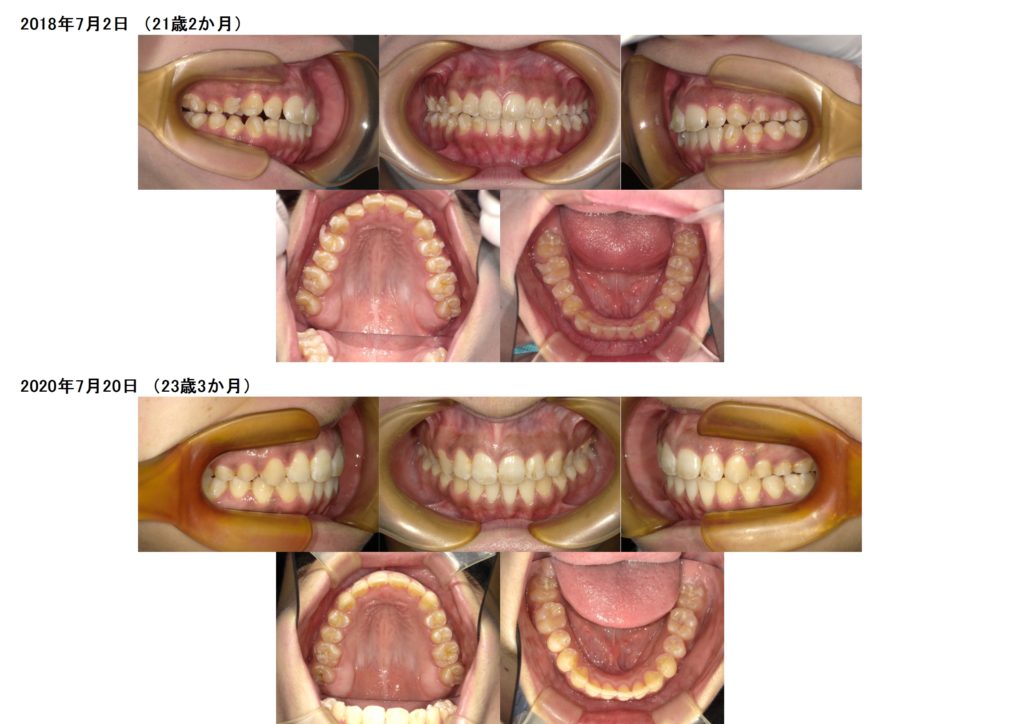

今回は、叢生(ガタガタ歯並び)、噛み合わせの治療をマウスピース、アライナーを使用した治療例になります。

上下の写真を見比べてみると上下の顎の土台をしっかりと整ったのが分かると思います。

特に、上のアーチの形が変わったのが分かりますよね☆

しっかりとマウスピース、アライナーをルール通り装着時間を守って使用していただくと、とてもきれいに早く治療を終えることが出来ます。

ここから、リテーナーと呼ばれる保定装置を使用して頂くのですが、リテーナーでも、少しの動きをする事が可能なので、微調整をしながら、しっかりと保定をしていきます☆